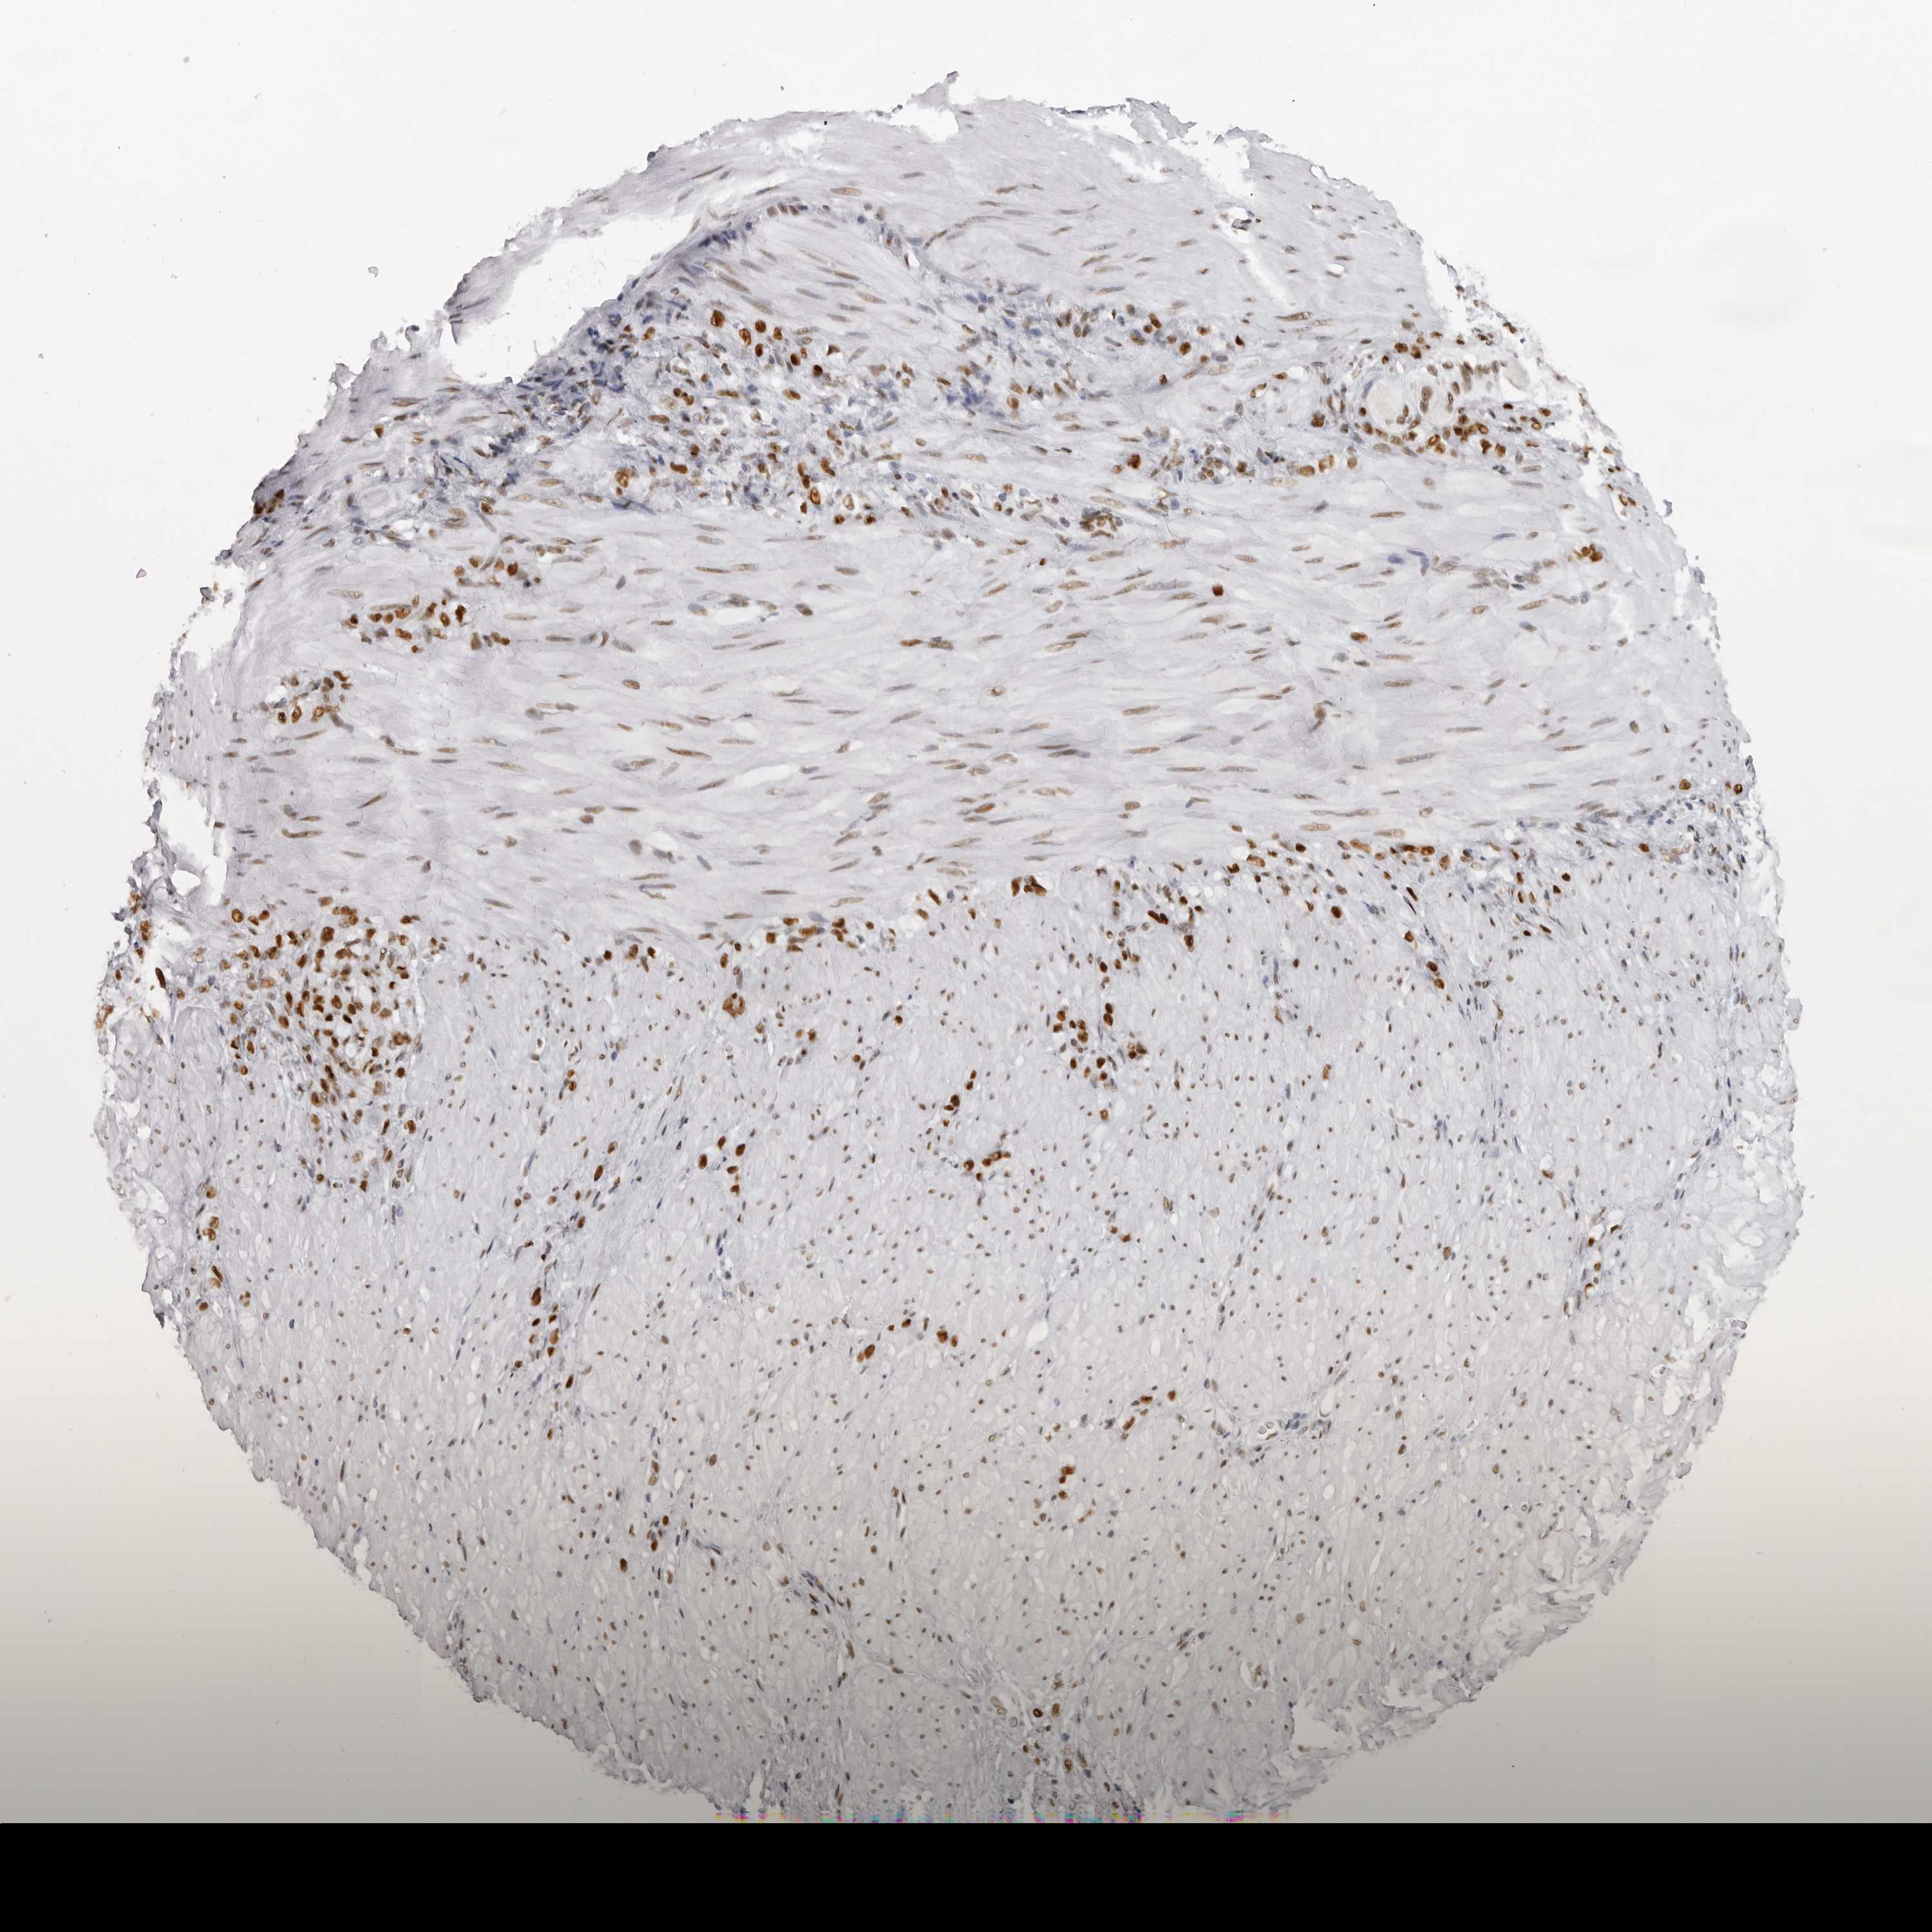

STOMACH CANCER - Protein expressioni

A mouse-over function shows sample information and annotation data. Click on an image to view it in a full screen mode. Samples can be filtered based on level of antibody staining by selecting one or several of the following categories: high, medium, low and not detected. The assay and annotation is described here.

Antibody stainingi

Antibody staining in the annotated cell types in the current human tissue is reported as not detected, low, medium, or high, based on conventional immunohistochemistry profiling in selected tissues. This score is based on the combination of the staining intensity and fraction of stained cells.

Each image is clickable and will lead to virtual microscopy that enables deeper exploration of all samples and also displays staining intensity scores, fraction scores and subcellular localization as well as patient and tissue information for each sample.

Antibody HPA027815

Staining

High

Medium

Low

Not detected

Intensity

Strong

Moderate

Weak

Negative

Quantity

>75%

75%-25%

<25%

None

Location

Nuclear

Cytoplasmic/membranous

Cytoplasmic/membranous,nuclear

Adenocarcinoma, NOS